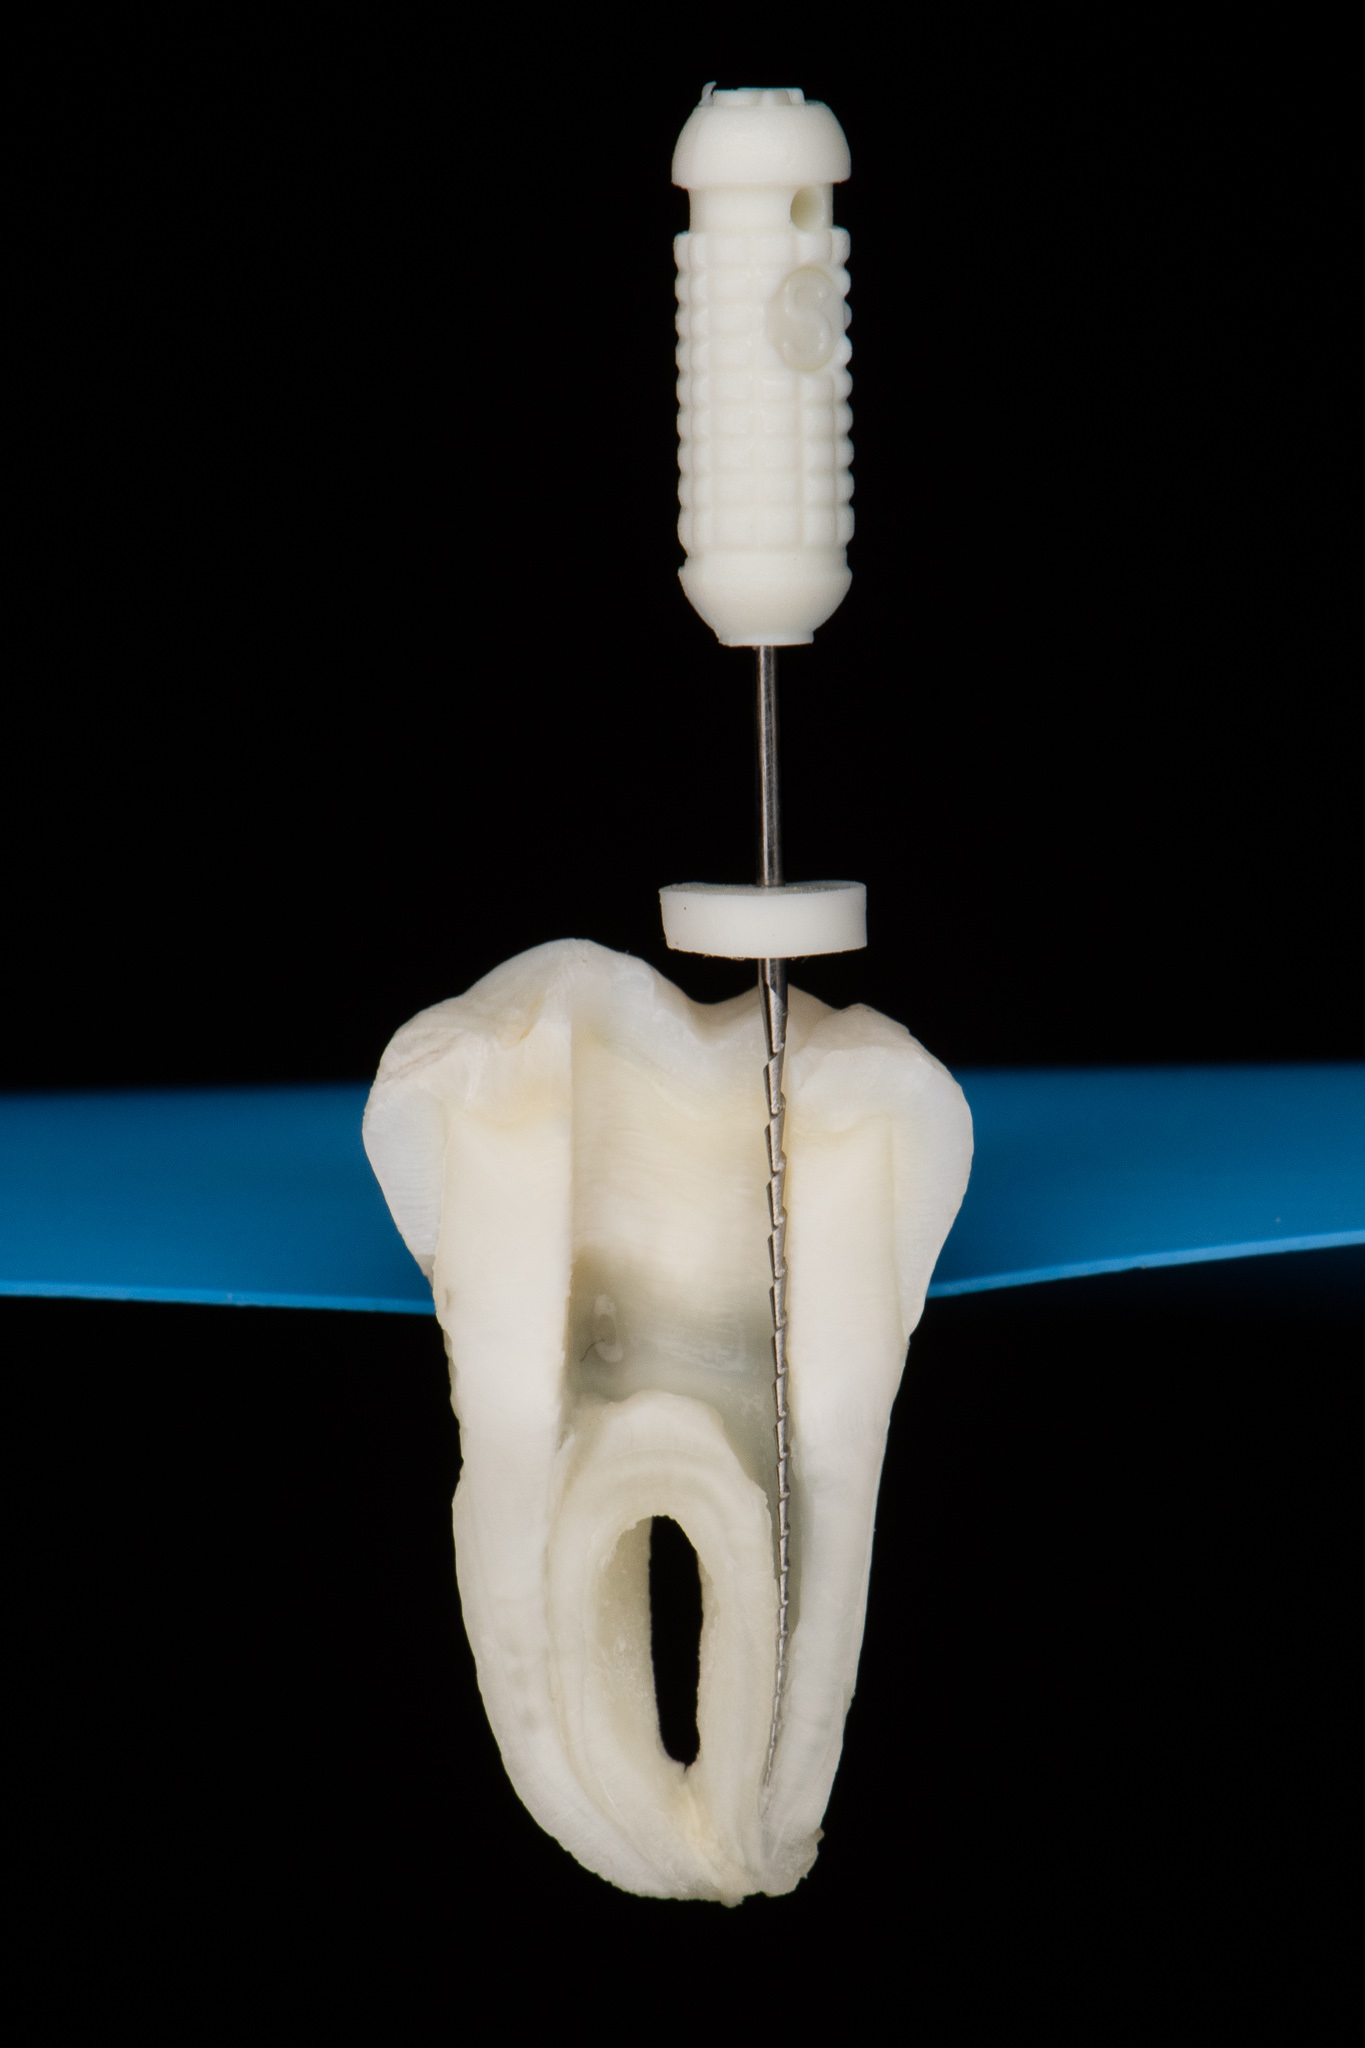

Endodoncja czyli leczenie kanałowe pozwala, na wiele lat, utrzymać w zdrowiu zęby martwe, które w przeciwnym razie wymagałby usunięcia. W naszym gabinecie prowadzimy leczenie kanałowe pierwotne jak również powtórne (ReEndo) z wykorzystaniem nowoczesnych technik i narzędzi takich jak mikroskop zabiegowy, rotacyjne systemy udrażniania kanałów czy wypełnienie płyną falą gutaperki.

Pacjent zgłosił się do gabinetu w celu zaopatrzenia złamanego zęba (kła) w koronę protetyczną. W badaniu radiologicznym widoczna jest resorpcja materiału wypełniającego kanał po dawnym leczeniu endodontycznym oraz tworząca się zmiana zapalna w okolicy wierzchołka korzenia; z uwagi na konieczność wykorzystania zęba jako filar protetyczny przeprowadzono powtórne leczenie kanałowe (ReEndo) z wykorzystaniem nowoczesnych narzędzi rotacyjnych oraz mikroskopu zabiegowego. Kanał wypełniono szczelnie techniką obturacji płynną falą gutaperki (wypełnienie na ciepło).